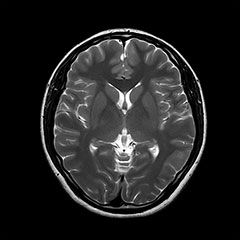

MRI

脳卒中、脳腫瘍、脳萎縮、白室病変、脳室拡大

日本脳ドック学会の推奨する検査内容となります。 頭部MRI検査(T1WI, T2WI, FLAIR, T2*)、頭部MRA検査、頚動脈MRA検査、血液検査、尿検査、心電図検査を行います。